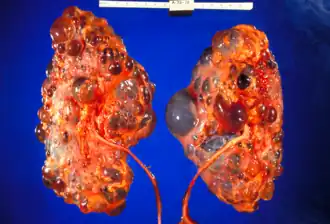

![]() Riñones poliquísticos gravemente afectados extirpados en el momento del trasplante | ||